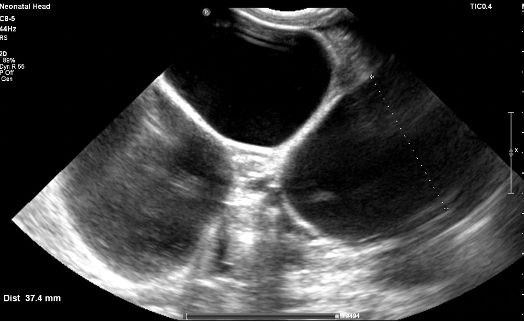

Preterm premature rupture of membranes (pPROM) before 22–24 weeks of gestation is considered previable and poses a high risk to the chances of successful delivery. Multicystic dysplastic kidney (MCDK) is the most common form of dysplasia of this organ, usually affecting 1 kidney. A prenatal suspicion of MCDK requires escalation of the clinical process to a reference center qualified and equipped for further diagnosis and treatment. We present a unique case of prenatal pPROM at 19 weeks of gestation in a pregnancy complicated by fetal MCDK as an interesting obstetric and neonatal patient story. We have not found any published evidence on the impact of coexisting fetal congenital malformations on a pregnancy affected by previable pPROM.

Balasundaram M, Chock VY, Wu HY, Blumenfeld YJ, Hintz SR. Predictors of poor neonatal outcomes in prenatally diagnosed multicystic dysplastic kidney disease. J Perinatol 2018;38(6):658-64.